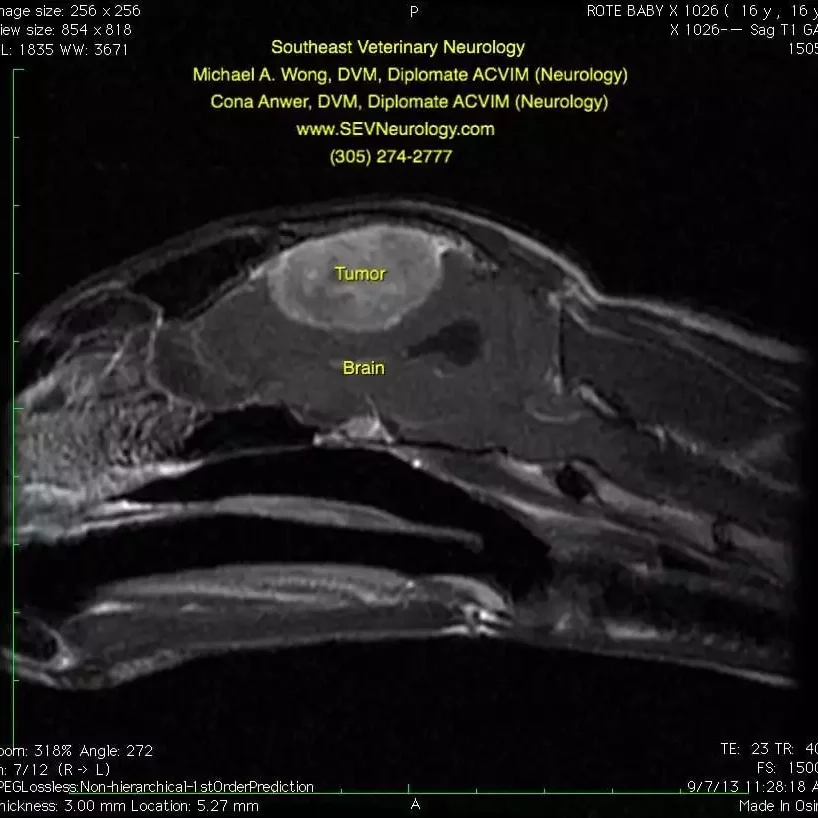

This first image is a sagittal, T2-weighted MRI of Baby’s head. The nose is toward the left and the top of the head is toward the top of the image. Note the evidence of mass effect--the brain tissue is being pushed down by the mass. The cerebellum is normally round, but you can see how it is being squashed toward the right and that there is herniation (arrow) of the cerebellum. A computed tomography (CT) scan would not show these changes.